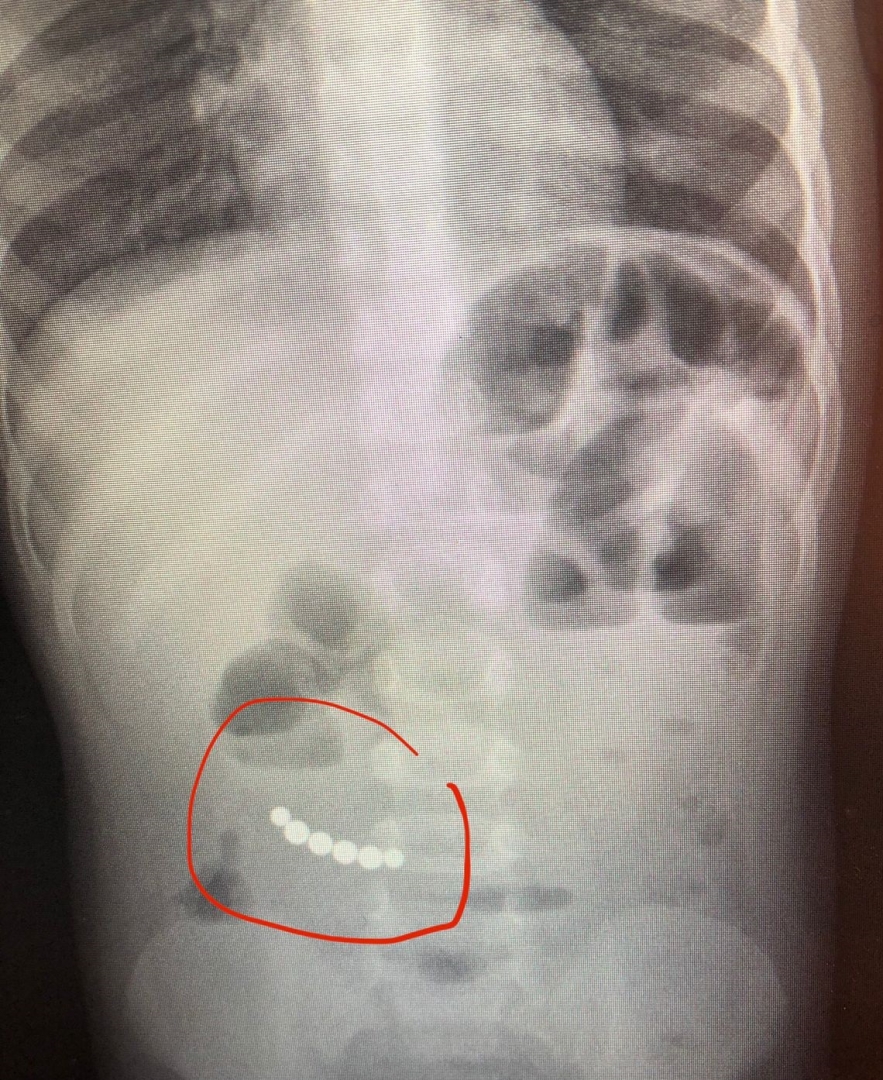

Рентген брюшной полости показал, что в кишечнике ребенка находятся шесть округлых инородных тел. Расспросили родителей и выяснили, что недавно ему подарили игрушку-конструктор, состоящую из шарообразных магнитов.

В экстренном порядке была проведена операция. Как рассказал детский хирург больницы Николай Гришин, при ревизии брюшной полости были обнаружены инородные тела – 6 магнитов из игрушки-конструктора. В ходе операции удалили их и устранили кишечную непроходимость.